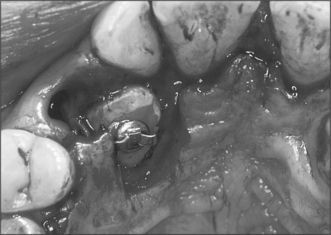

3. In Fig. 12.18 the upper right canine tooth has been surgically exposed.

(a) Describe the type of flap that has been used.

(b) Why has the excess tissue not been surgically excised at the same time?

(c) What other technique can be used to prevent the defect healing?

(d) What else could be done at the time of surgery to encourage eruption of the tooth?